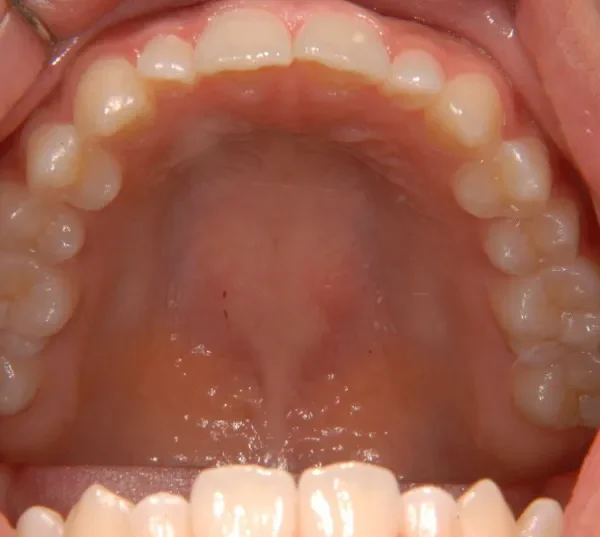

開咬・舌癖・18歳女性

初診時年齢 高校生 (女性) 主訴 開咬 舌癖

状態 前歯で噛めない(開咬/オープンバイト)